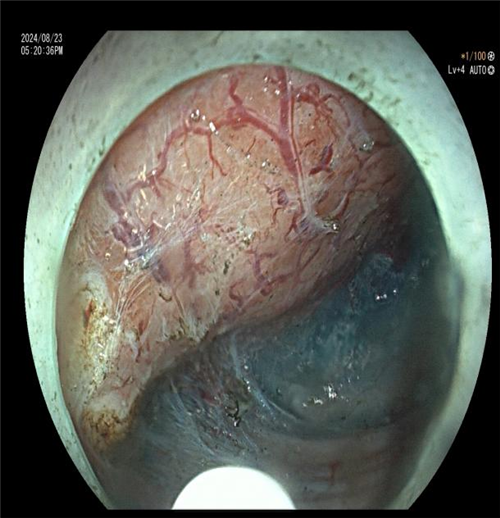

近日,一位患者因 “反复上腹胀痛、纳差 1 年余” 入住我院普外二科(胃肠外科)。入院肛检发现直肠后壁有大块颗粒样增厚区,CT 提示直肠壁增厚。进一步肠镜检查后,内镜下见直肠约 6*5cm 侧向发育型息肉,下缘距肛门仅 2.5cm,活检病理为绒毛状管状腺瘤。

科主任曾春辉在与患者及家属商讨手术方式时,了解到患者极度排斥外科手术,因其病变位置特殊,距离肛门仅 2.5cm,开刀恐难以保住肛门,患者表示宁愿不做手术也不愿生活质量低下。尽管病变巨大且位置特殊,内镜手术难度大、风险高,已超出常规 ESD 手术范畴,但曾主任毅然决定挑战技术极限。他在全麻下为患者施行 “内镜下直肠下段侧向发育息肉 ESD 术(隧道内镜技术)”,手术顺利完成。